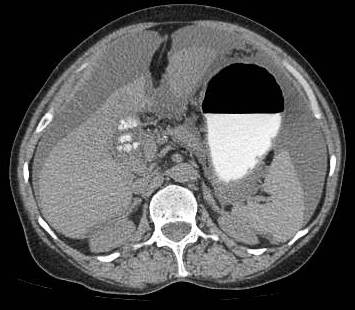

Common patterns of carcinoma gallbladder

Three patterns have been described on ultrasonography (US). The gallbladder fossa is replaced by a heterogeneous mass (figure 1) with internal areas of necrosis; or there may be diffuse, irregular, and asymmetrical wall thickening (Figure 2); or less commonly, a polypoidal, fungating intra-luminal mass is seen. Correct preoperative diagnosis has improved considerably with the use of newer imaging techniques [6-8]. Majority of cases when diagnosed, are no longer resectable (Figure 3) [9-11].

Figure 1: large gallbladder fossa mass replacing the entire gall bladder. Discrete liver secondaries can be seen.

Figure 1: Large gallbladder fossa mass replacing the entire gallbladder. Discrete liver secondaries can be seen.